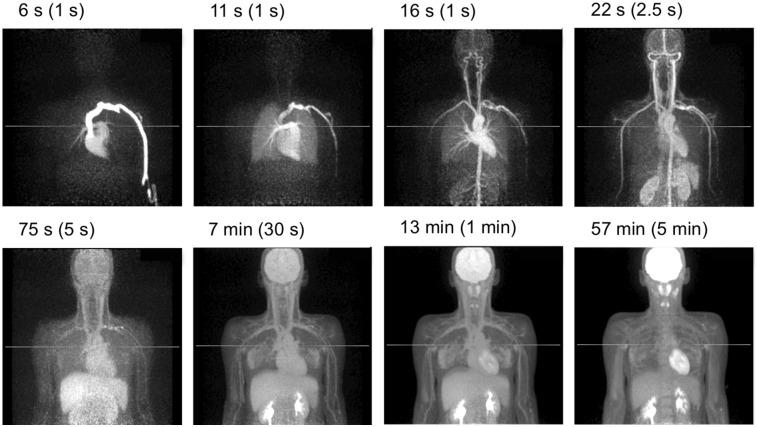

We report on the development of the PennPET Explorer whole-body imager. The PennPET Explorer is a multiring system designed with a long axial field of view. The imager is scalable and comprises multiple 22.9-cm-long ring segments, each with 18 detector modules based on a commercial digital silicon photomultiplier. A prototype 3-segment imager has been completed and tested with an active 64-cm axial field of view. The instrument design is described, and its physical performance measurements are presented. These include sensitivity of 55 kcps/MBq, spatial resolution of 4.0 mm, energy resolution of 12%, timing resolution of 256 ps, and a noise-equivalent count rate above 1,000 kcps beyond 30 kBq/mL. After an evaluation of lesion torso phantoms to characterize quantitative accuracy, human studies were performed on healthy volunteers. The physical performance measurements validated the system design and led to high-quality human studies.

我们报告了 PennPET Explorer 全身成像仪的开发情况。PennPET Explorer 是一款多环系统,设计具有长轴向视野。该成像仪具有可扩展性,由多个 22.9 厘米长的环段组成,每个环段都有 18 个基于商用数字硅光电倍增管的探测器模块。已经完成了一个具有主动 64 厘米轴向视野的 3 段式原型机,并进行了测试。本文描述了仪器的设计,并介绍了其物理性能测量结果。这些结果包括 55 kcps/MBq 的灵敏度、4.0 毫米的空间分辨率、12%的能量分辨率、256 ps 的时间分辨率以及在 30 kBq/mL 以上超过 1000 kcps 的噪声等效计数率。在对用于定量准确性评估的病灶体模进行评估后,我们在健康志愿者中进行了人体研究。物理性能测量验证了系统设计,并实现了高质量的人体研究。